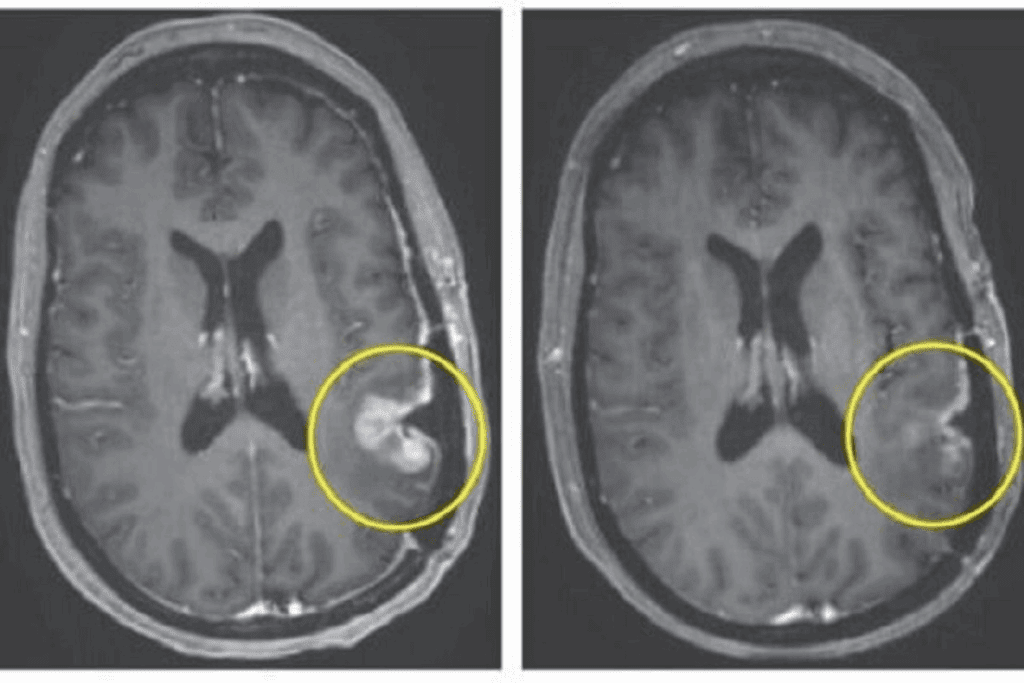

To diagnose neuroblastoma, doctors use imaging like ultrasound and CT scans, along with a biopsy. The diagnosis of neuroblastoma is key to figuring out the stage and risk. This helps decide the best treatment.

Complete remission in neuroblastoma means all disease signs have vanished after treatment. Tests like imaging and bone marrow exams show no tumor cells. This is a big win in the treatment journey, showing a good response to therapy.

We see complete remission as a major goal in neuroblastoma treatment. It’s linked to better survival rates and quality of life. Yet, it’s vital to remember that it doesn’t mean the disease is completely gone. There’s always a chance it could come back.